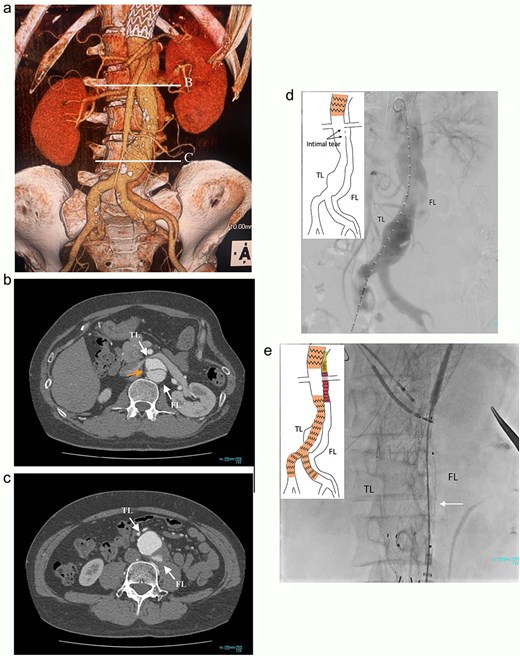

A 46-year-old man, with a history of noncompaction cardiomyopathy, underwent emergency zone 3 thoracic endovascular aortic repair (TEVAR) using TAG (WL Gore & Associates, Newark, DE, USA) for complicated type B acute aortic dissection. Postoperative contrast-enhanced computed tomography (CT) imaging showed the FL began from the descending aorta and extended into the left external iliac artery (EIA) (Fig. 1a), and several residual re-entries at the renal artery level (Fig. 1b) and one at the left EIA level. Both renal arteries were also originated from the true lumen. Both the FL and the post-dissection TAAA were dilated to diameters of 23 and 53 mm, respectively (Fig. 1c). Considering impaired cardiac function with the ejection fraction of 24%, the endovascular treatment was performed with intimal tear closure using FL stent graft placement as previous study reported [1]. First, endovascular aortic repair (EVAR) was completed with Excluder Aortic Extender (WL Gore & Associates, Newark, DE, USA) below the renal artery, followed by Excluder main body (WL Gore & Associates, Newark, DE, USA) landing on bilateral common iliac arteries. This excluded abdominal aortic aneurysm. Second, we placed a 10 × 40 mm Epic vascular self-expanding stent (Boston Scientific, Marlborough, MA, USA) in the FL at the level of distal end of the TAG. Then, the intimal tears at the renal artery level were closed using Endurant II iliac leg (cat No. ELW1624C94 Medtronic, Dublin, Ireland) from the FL side, overlapping with Epic stent proximally, and Aortic Extender distally (Fig. 1d and e). The retrograde angiography from left femoral artery sheath showed residual blood flow blowing up into the FL from the re-entry at the left EIA, and some lumbar arteries originating from the FL were contrasted.

Preoperative CT 3D reconstruction showing the FL extended from the descending aorta to the external iliac artery (a), contrast-enhanced CT axial images at the renal artery level with an intimal tear (b; arrow), and the abdominal aortic aneurysm level (c), and the intraoperative angiography showing the FL were contrasted through intimal tear at the visceral segment (d), Endurant II iliac leg placed in the FL closing intimal tears near the renal artery (e; white arrow). TL: true lumen; FL: false lumen.